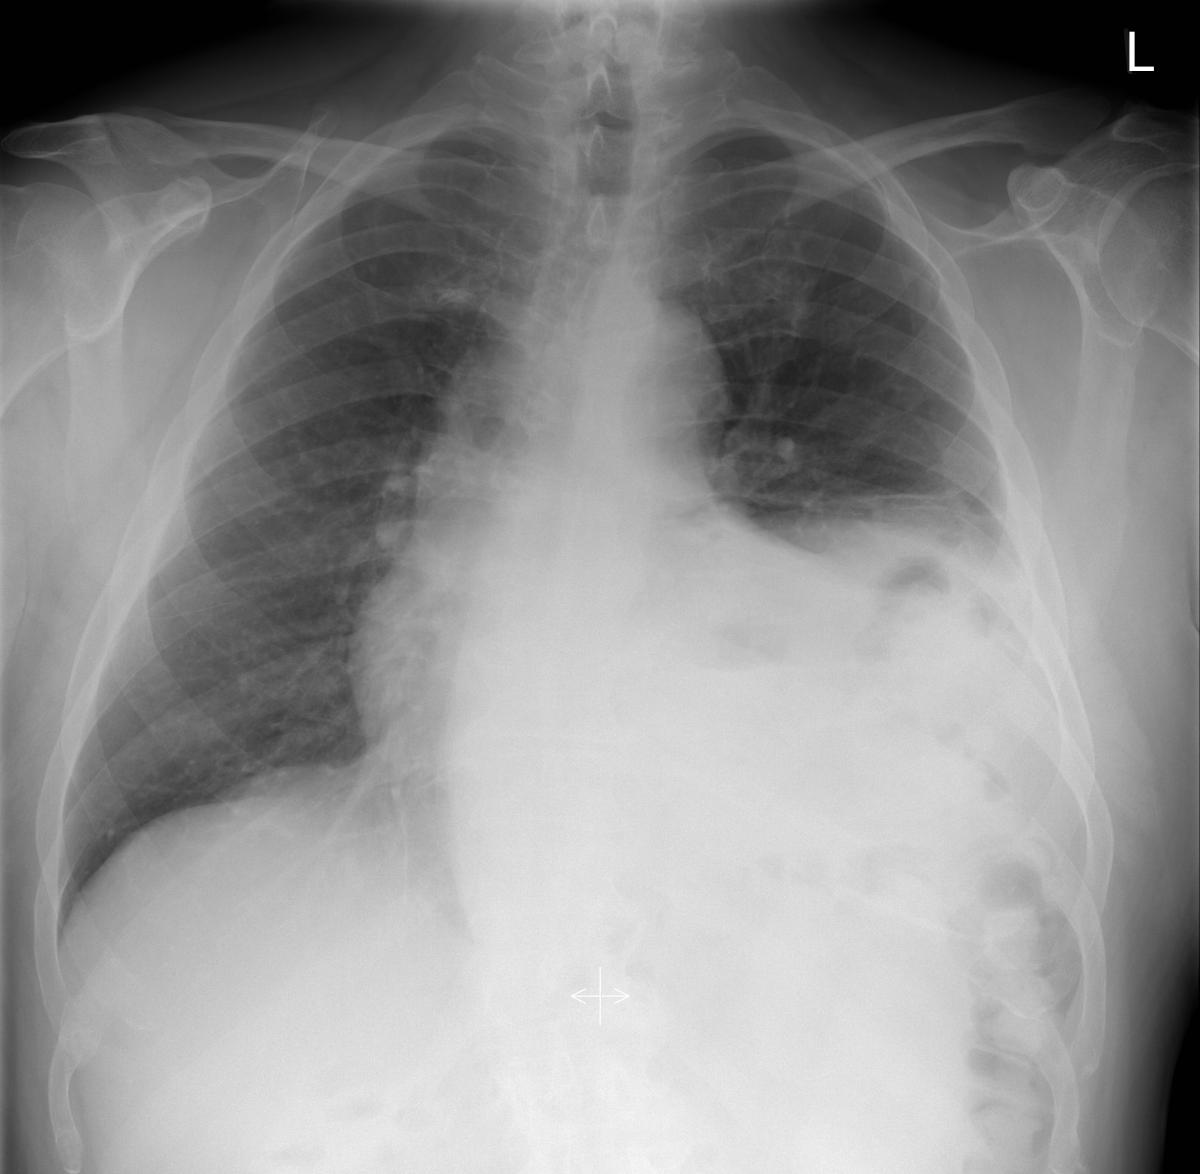

Figure 1 from Transabdominal robotassisted diaphragmatic plication a Robotic Assisted Diaphragmatic Plication with the advent of robotic minimally invasive techniques, diaphragm plication can be a useful therapy for patients with resolution of symptoms, reduced length of hospitalization, and quickened recovery. a robotic diaphragm plication lasts around one hour. Though their etiology and pathology are. Robotic Assisted Diaphragmatic Plication.